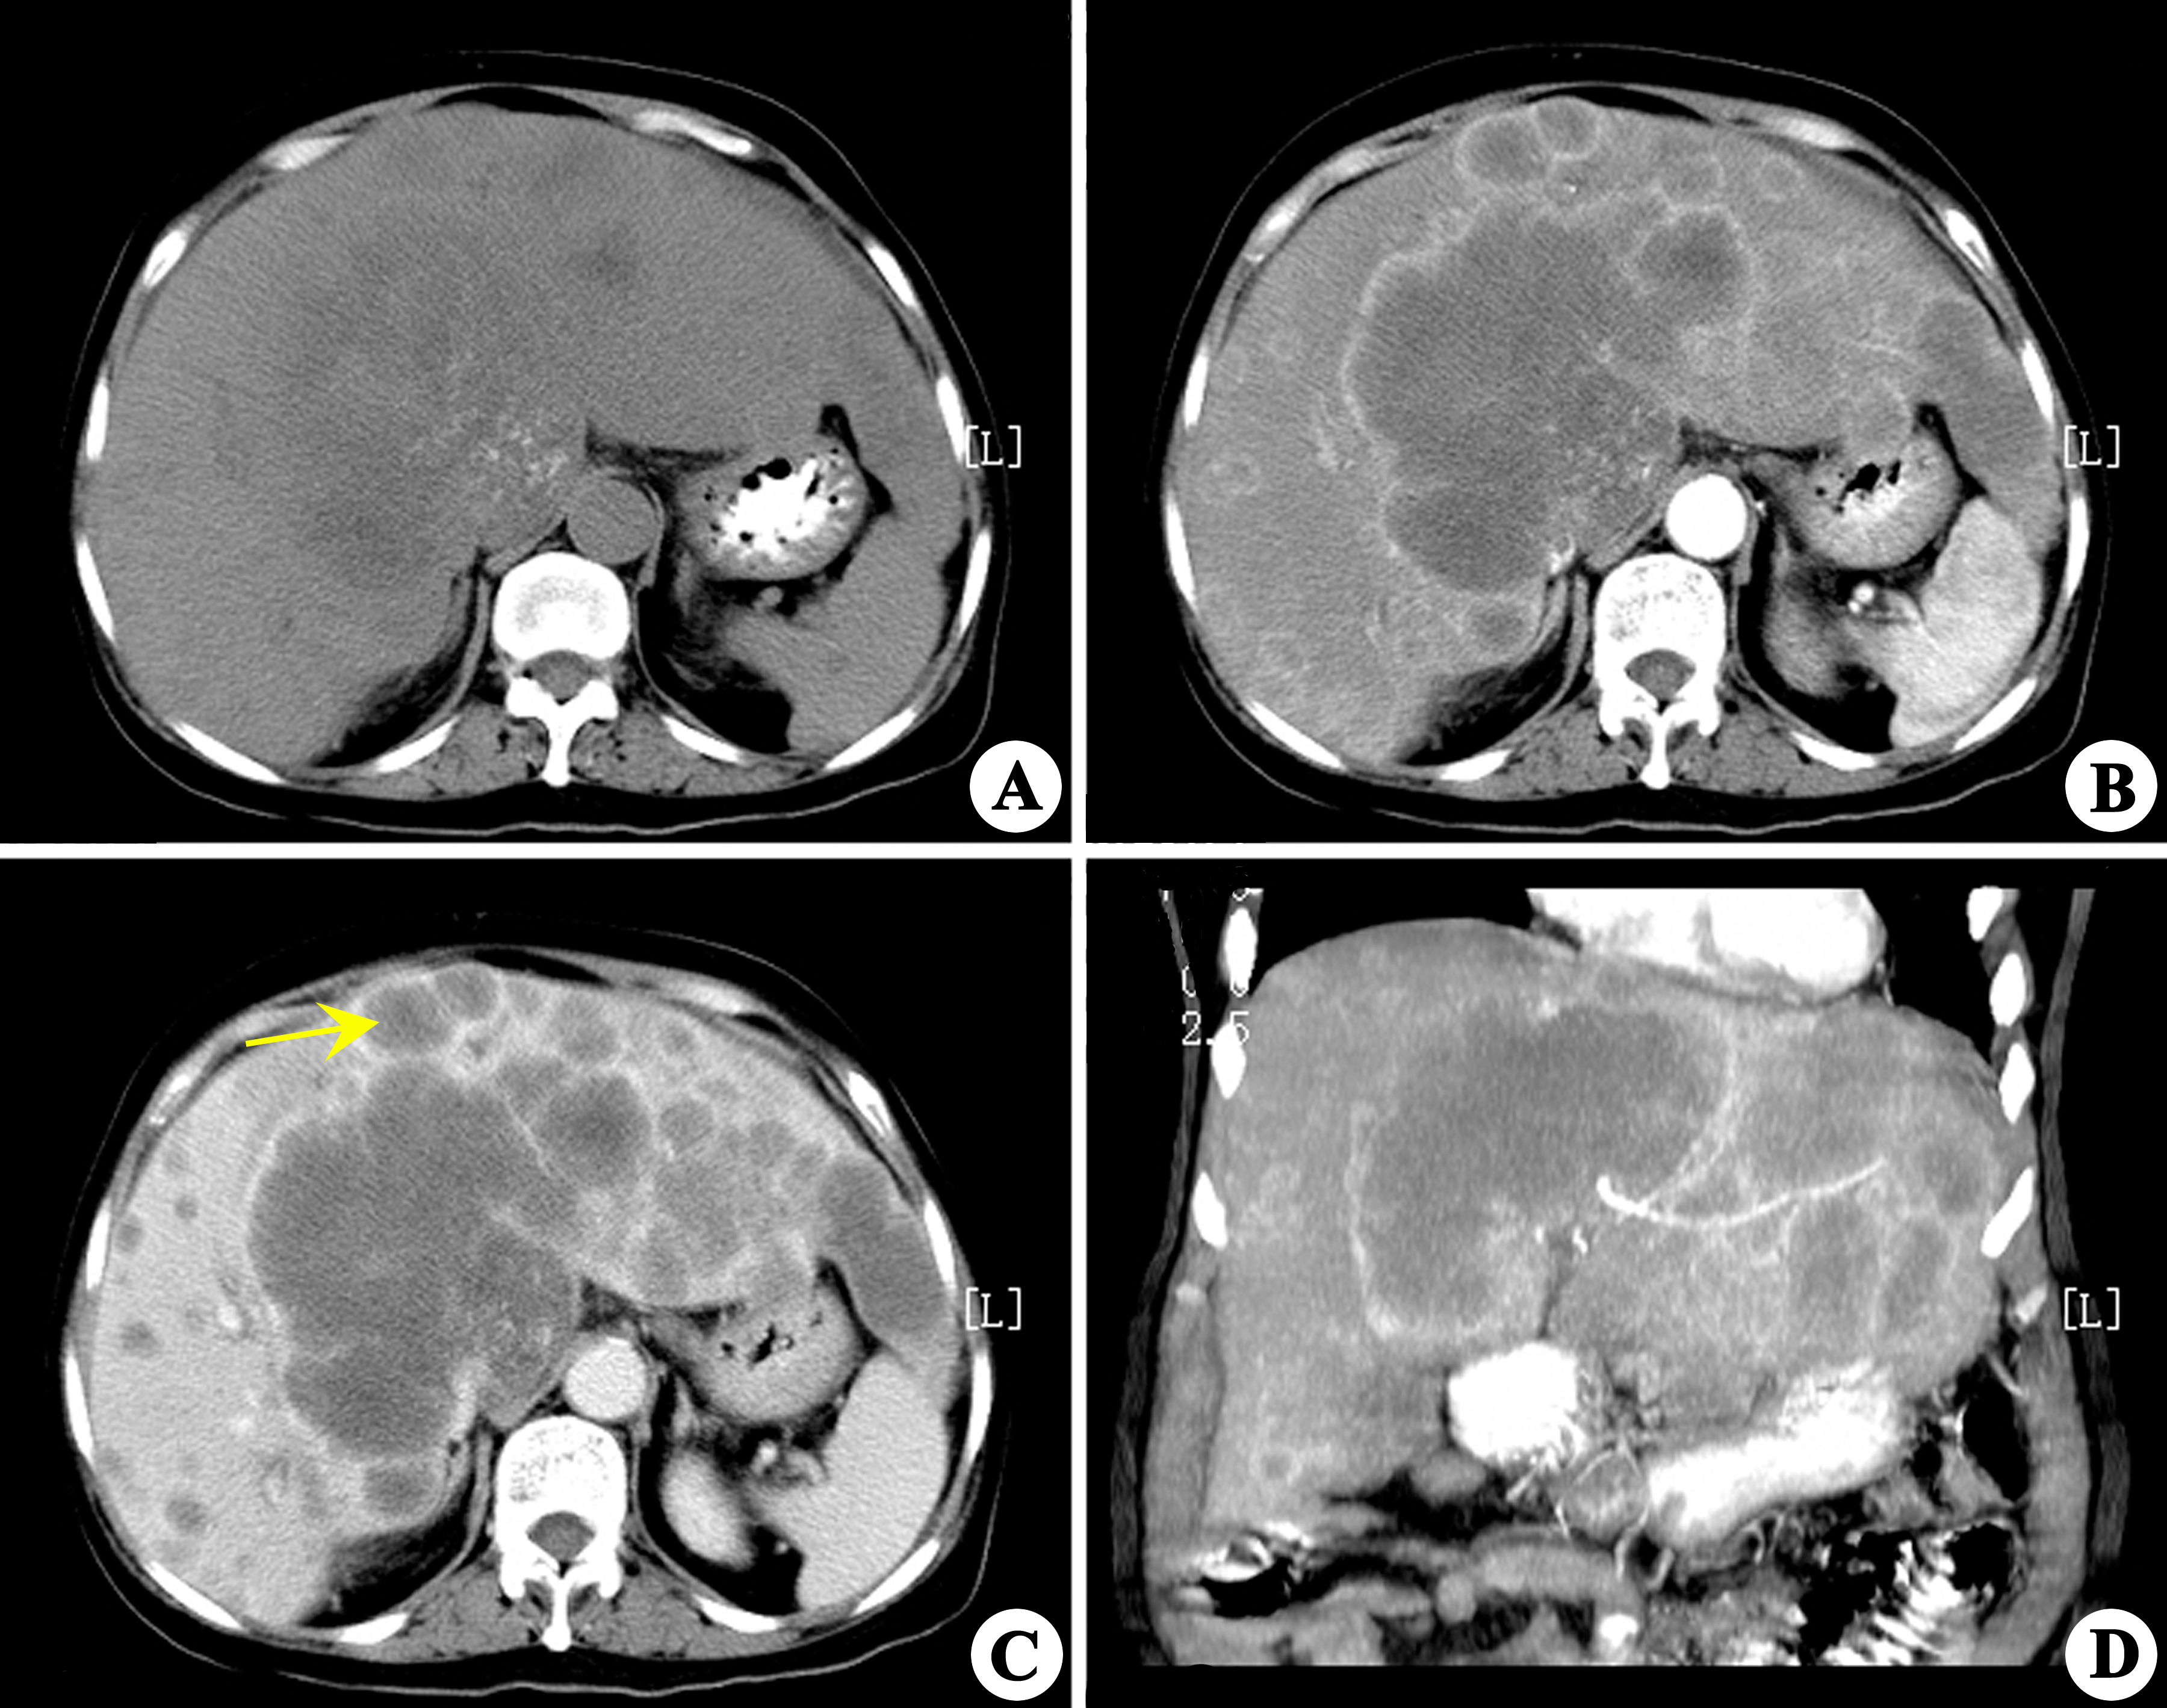

入院后行腹部ct提示升结肠,结肠肝曲占位病变,考虑:肿瘤样变伴临近

内镜:结肠肝曲新生物伴肠腔狭窄(距肛缘68cm左右)

结肠肿瘤位于升结肠肝曲约10×10×10cm大小,侵出浆膜.